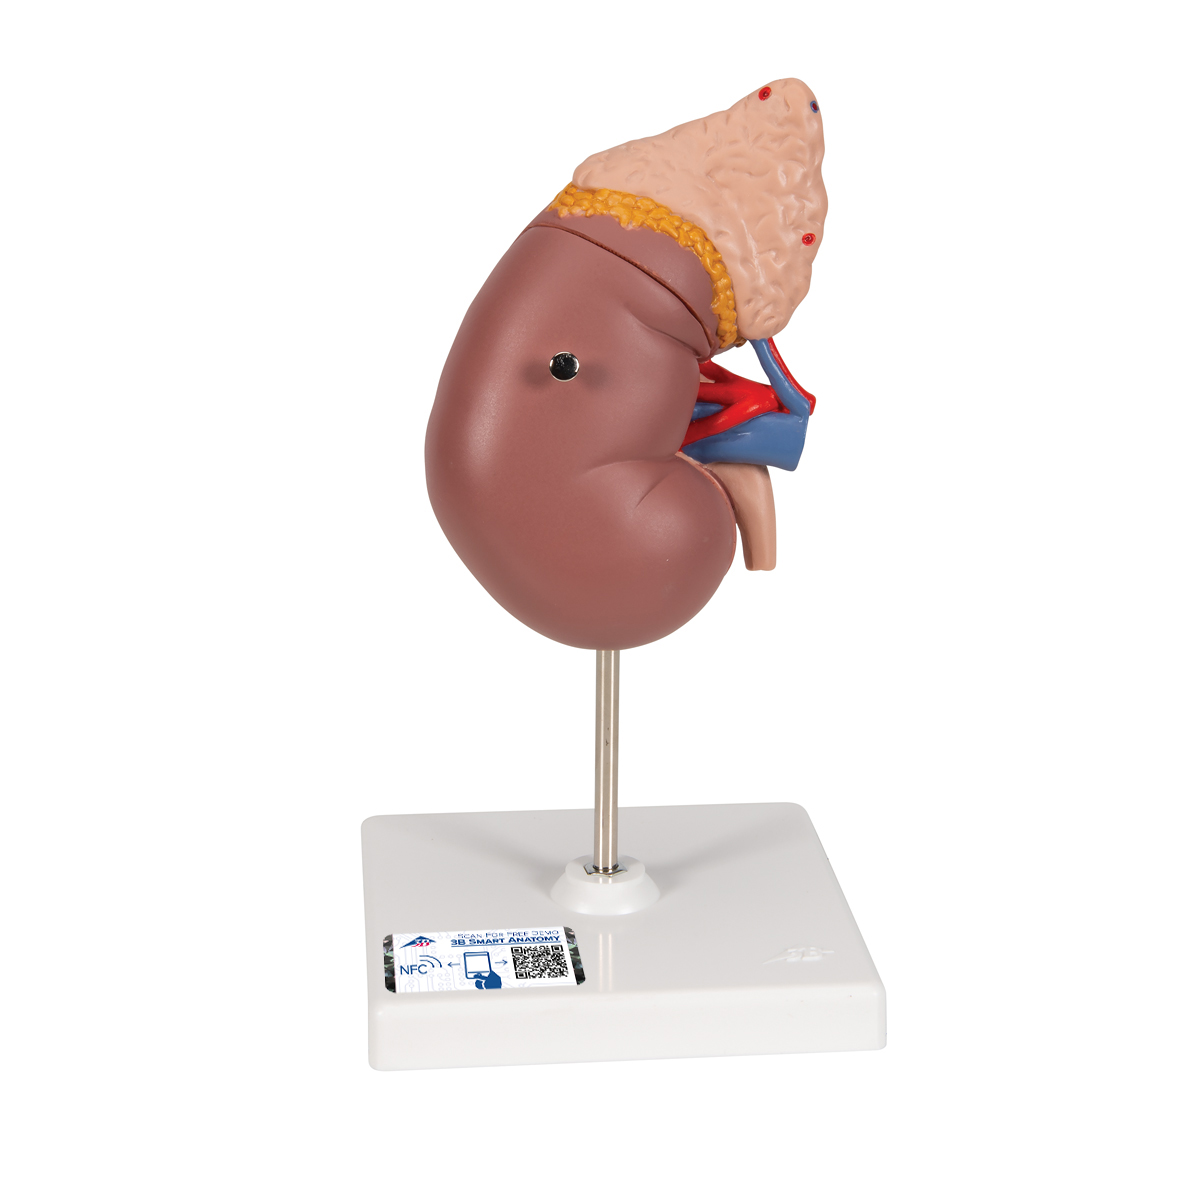

Эта модель в натуральную величину демонстрирует почки с надпочечниками, мочеточники, внутрипочечные сосуды и крупные кровеносные сосуды, расположенные в непосредственной близости от почек. Съемная передняя половина правой почки позволяет увидеть почечную лоханку, чашечки, корковый и мозговой слои почки. На подставке.